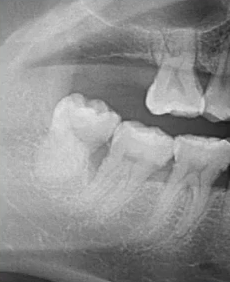

比如下面这张片子显示出的龋坏合并根尖周炎。

因为曲面断层片反映的是上下颌牙齿、上颌窦、关节,在一张片子中所展示的解剖结构较多。比如刚才的片子,最容易诊断的是右下6远中邻面深龋合并根尖周炎,左下有埋伏的多生智齿,右侧是垂直智齿。